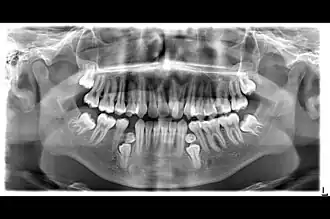

Radiografia Panorámica de Paciente con Hiperdoncia

Si bien un solo exceso de diente es relativamente común, la hiperdoncia múltiple es rara en personas sin otras enfermedades o síndromes asociados. Muchos dientes supernumerarios nunca entran en erupción, pero pueden retrasar la erupción de los dientes cercanos o causar otros problemas dentales o de ortodoncia. Los dientes adicionales de tipo molar son la forma más rara. Las radiografías dentales a menudo se usan para diagnosticar la hiperdoncia.